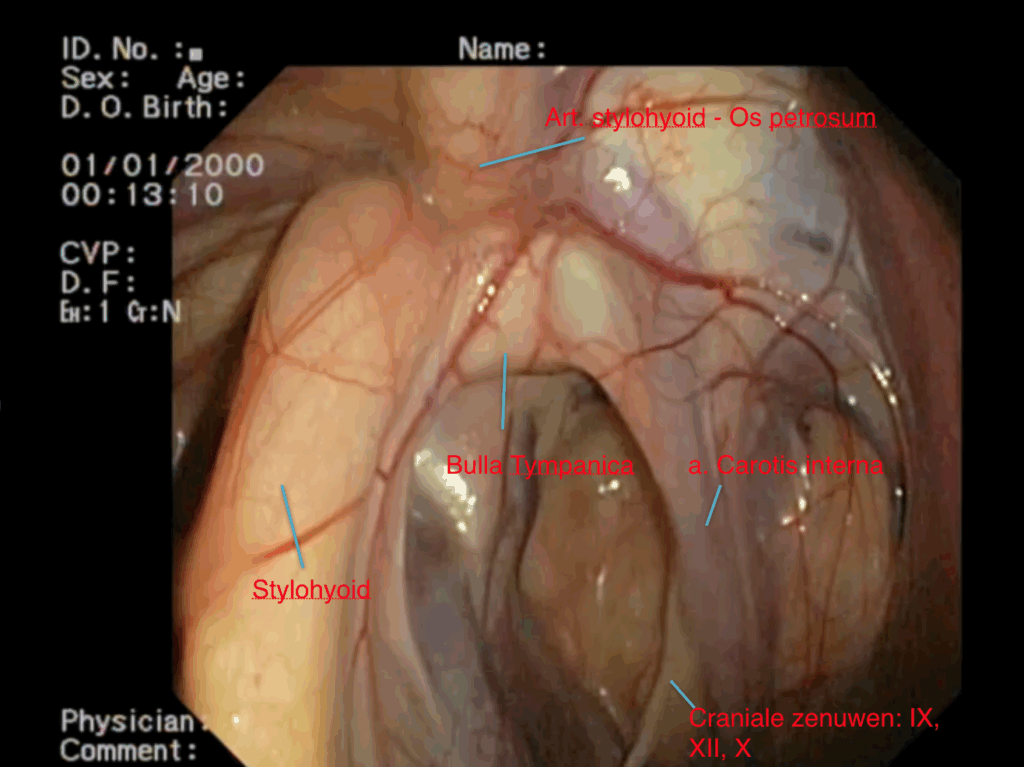

Některé z hlavních cév zásobujících hlavu se nacházejí v těsné blízkosti stěn vzdušných vaků. Jedná se zejména o hlavní tepnu (krkavici), která vystupuje přímo ze srdce a zásobuje kyslíkem hlavu a mozek. Na úrovni hlavy se tato tepna rozdělí do několika silných tepenných větví, které procházejí stěnami vzdušných vaků (vnější a vnitřní větev krkavice a čelistní tepna, obr. 2).

Hlavové nervy vybíhají z mozkového kmene a inervují struktury v blízkosti hlavy. Je jich celkem dvanáct. Některé z těchto nervů (IX, X, XII) procházejí vzdušnými vaky a mohou při mykóze vaků způsobovat typické neurologické potíže. Jazykohltanový nerv (IX) inervuje svaly jazyku a hrdlo. Bloudivý nerv (X) je velmi důležitý nerv, který inervuje velké svaly, jako jsou hlasivky a svaly hrtanu. Podjazykový nerv (XII) inervuje mimo jiné i jazyk (obr. 2).